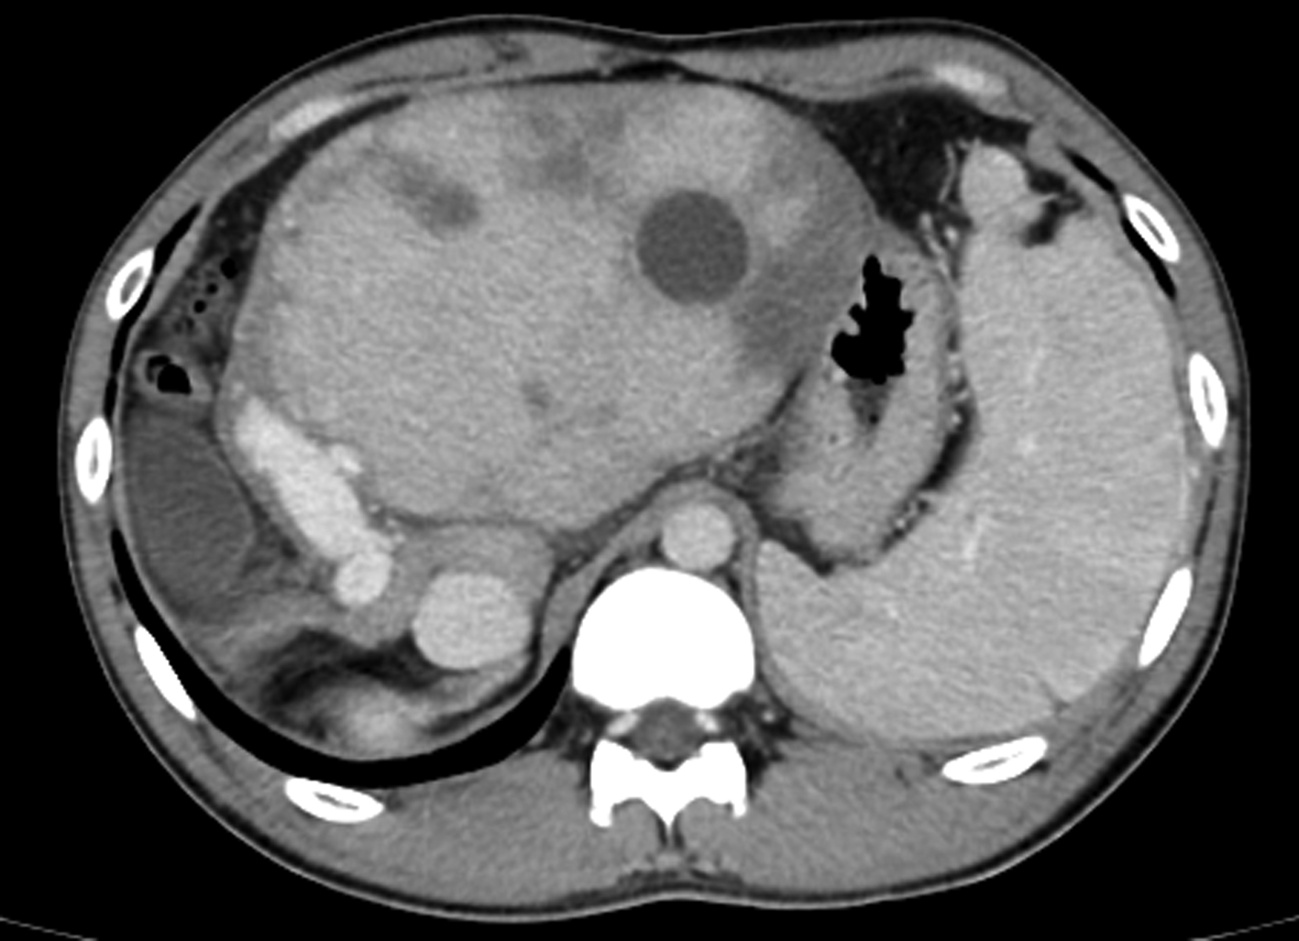

Short-term mortality and death causes after TACE in patients with primary liver cancer

Zhao LIU, Zhi LI, Kailun YANG, Siyin LI, Xiaoli ZHU, Caifang NI

2022, 38(11): 2510-2513. DOI: 10.3969/j.issn.1001-5256.2022.11.014

Abstract(1479) HTML (241) PDF (2070KB)(80)

Abstract:

Objective  To investigate the short-term mortality of transcatheter arterial chemoembolization (TACE) in patients with primary liver cancer, and explore the possible causes of death and countermeasures.  Methods  All patients who underwent TACE at the Department of Interventional Radiology, First Affiliated Hospital of Soochow University from January 2015 to December 2020 were studied, but those with metastatic liver cancer or receiving combined treatment were excluded. The clinical and imaging data of all patients were collected before and 30 days after TACE, and the clinical characteristics of the patients with short-term postoperative death were analyzed. Death within 30 days after TACE was defined as short-term death.  Results  A total of 1466 TACE in 741 patients with primary liver cancer were included. Ten patients (10/741, 1.35%) died within 30 days after TACE, with a mortality rate of 0.68% for all TACE. The mortality rate of d-TACE and c-TACE was 1.62% (3/185) and 0.55 % (7/1281), respectively. The mortality rates of patients at China Liver Cancer Staging Ⅰ, Ⅱ, and Ⅲ stages were 0.45% (2/448), 0.33% (2/599), and 1.43% (6/419), respectively. The mean diameter of the largest lesion in death cases was 10.1±0.8 cm. The possible causes of death were liver failure (4 cases), rupture bleeding (3 cases), myelotoxicity (1 case), pulmonary embolism (1 case), and heart failure (1 case).  Conclusion  The mortality rate after TACE in patients with primary liver cancer is low, with occasional short-term postoperative deaths. The death cases are characterized by a large tumor volume, and the most common causes of short-term death are liver failure and rupture bleeding.